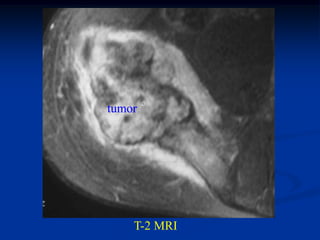

Case #640

15 year male with chondroblastoma proximal humerus

Coronal T-1 MRI

tumor

Coronal T-2 MRI

Photomic with giant cells

Another photomic